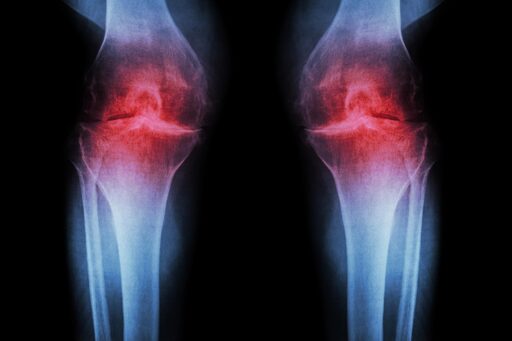

Researchers at Stanford Medicine report that blocking a protein linked to aging can restore cartilage that naturally wears away in the knees of older mice. In the study, the injectable treatment not only rebuilt cartilage but also stopped arthritis from developing after knee injuries similar to ACL tears, which are common among athletes and active adults. A pill-based version of the same therapy is already being tested in clinical trials aimed at treating muscle weakness associated with aging.

Human knee tissue collected during joint replacement surgeries also responded positively to the treatment. These samples, which include both the joint’s supporting extracellular scaffolding, or matrix, and cartilage-producing chondrocyte cells, began forming new cartilage that functioned normally.

Together, these findings point to the possibility that cartilage lost through aging or arthritis could one day be restored using a localized injection or an oral medication, potentially eliminating the need for knee or hip replacement surgery.